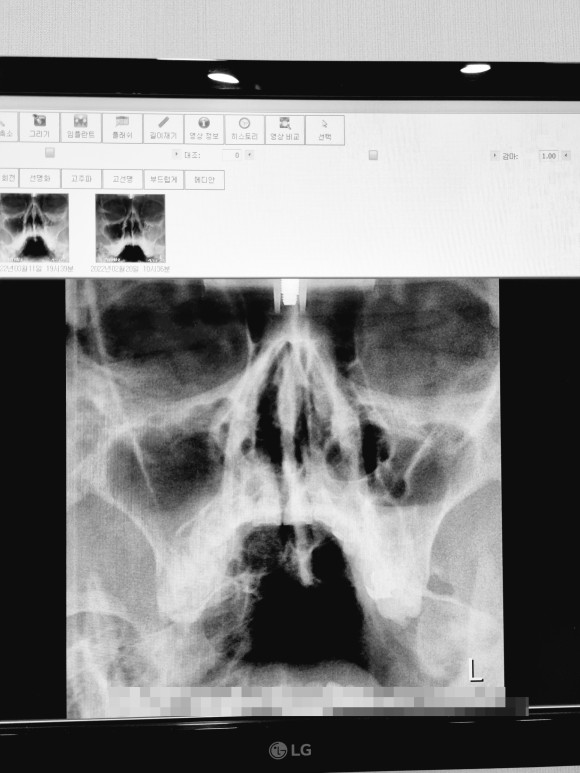

부비강염 치료

사진상으로는 아직 절반도 빠지지 않은 염증ㅠㅠ

부비강염

왼쪽에도 약간의 염증이 있지만 정상수준

오른쪽에는 반 이상 하얀 무언가가 가득 찬 그림이 보이시죠?

(새까맣게 비어있는 것이 정상입니다)